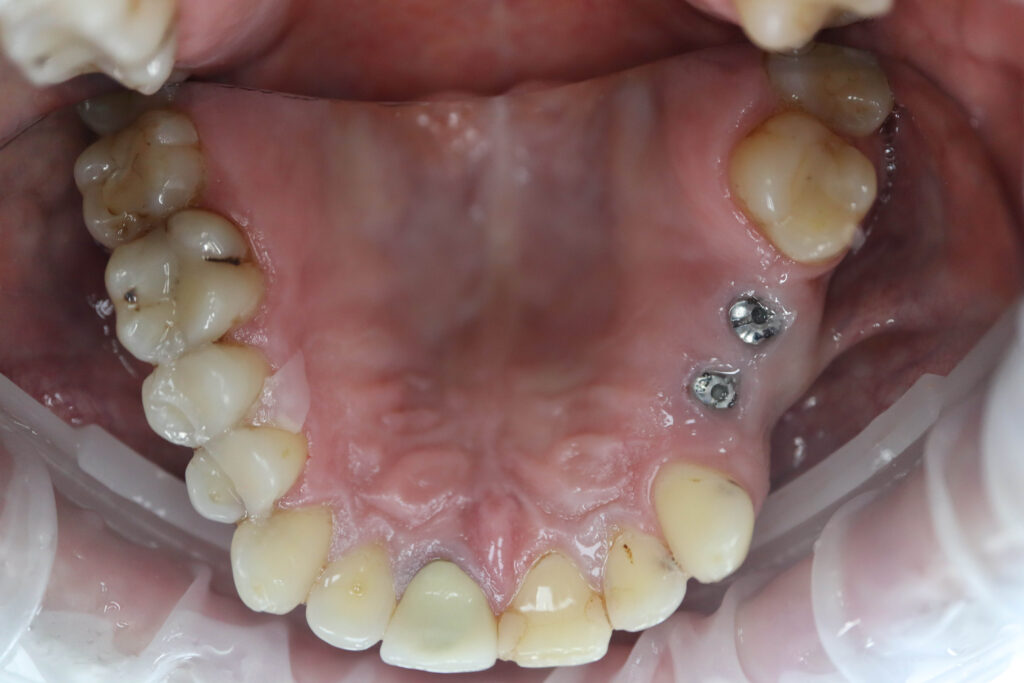

Процесс работы

Что было сделано:

На верхней и нижней челюстях были установлены 6 имплантатов Megagen Anyone.

процесс имплантации